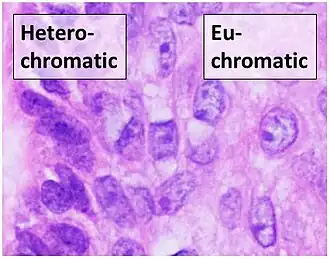

Sometimes "heterochromatic" versus "euchromatic" nuclei are used for visual appearance, but this strictly refers to the molecular structure of DNA.

Sometimes "heterochromatic" versus "euchromatic" nuclei are used for visual appearance, but this strictly refers to the molecular structure of DNA. -